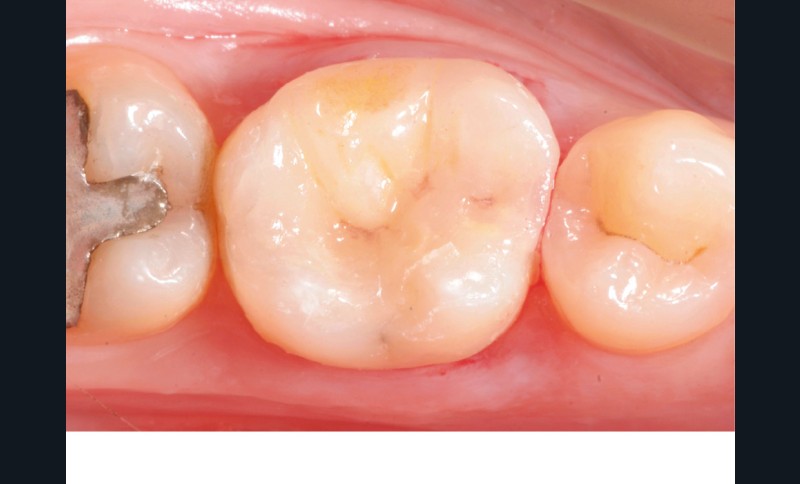

Lors de la préparation d’une cavité pour inlay/onlay, il est fréquent d’être confronté, en fin de nettoyage, à la présence d’une ou plusieurs parois résiduelles dont la résistance mécanique paraît douteuse du fait de leur localisation ou de leur épaisseur. Les parois épaisses (+ de 2 mm) peuvent généralement être conservées (cas clinique 1) et les parois fines (- de 1 mm) doivent généralement être recouvertes. Un inlay (en composite ou en céramique) est alors réalisé. Il doit avoir lui même, au final, une épaisseur globale minimale de 2 mm pour assurer sa résistance mécanique intrinsèque à la mastication. Si un recouvrement cuspidien est indiqué, la réduction occlusale doit donc se faire sur 2 mm de hauteur au minimum [1, 2].

Mais qu’en est-il des parois résiduelles d’épaisseur intermédiaire (entre 1 et 2 mm) (cas clinique 2) ?